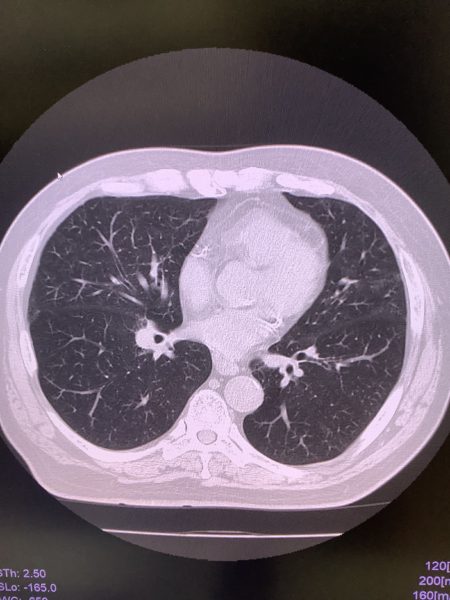

要精査の場合、肺の時はCT検査をさせていただくと思います。輪切りの状態で肺をみますので

詳細に診断できます。